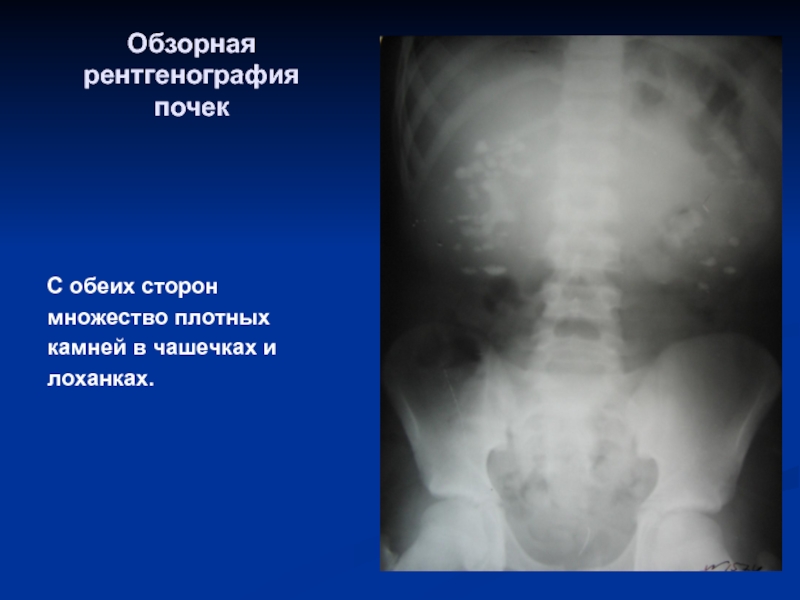

Медицинские изображения: Обзорная рентгенография урография

Раздел: Фокус на знании